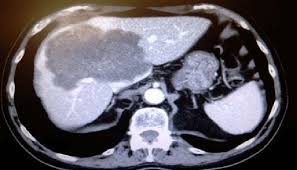

Colorectal cancers often spread before the initial tumor is detected, according to a new stanford study. This process by which cancer cells spread to other body parts is called metastasis. Cancer that starts in your colon can sometimes spread to other parts of your body, including the liver. Most cancer researchers have assumed that the spread, or metastasis, of tumors typically occurs later in the disease process. Biologic agents have assumed a major role in the treatment of metastatic cases. The process by which cancer cells spread to other parts of the body is called metastasis. Stage 4 colon cancer is the most advanced stage of the disease and may also be referred to as metastatic colon cancer. This means it has spread to regional or distant sites, such as other organs or lymph nodes. Colorectal cancer (crc) is the third most common cancer worldwide 1.approximately 56% of patients with crc die from their cancer 2.development of metastasis is a concern for patients and. With stage 3 colon cancer, there will be a positive finding of a primary tumor and regionally affected lymph nodes but no signs of metastasis. The most common site of metastases for colon or rectal cancer is the liver. Cancers that affect either of these organs may be called colorectal cancer. If the cancer spreads to other parts of the body, it is called metastatic colorectal cancer (mcrc), or stage 4 colorectal cancer.

Inhibition Of Ddr1 Bcr Signalling By Nilotinib As A New Therapeutic Strategy For Metastatic Colorectal Cancer Embo Molecular Medicine from www.embopress.org Christina curtis and her colleagues found that colon cancer tumors could. Metastatic colorectal cancer is cancer that has metastasized. Chemotherapy may also be used after surgery (called adjuvant treatment).most adjuvant treatment is given for about 6 months. This means that about 14% of people with stage iv colon cancer are likely to still be alive 5 years after they are diagnosed. Metastatic colon cancer is also a stage iv colon cancer. Mcrc is divided into three categories: Treatment for colon cancer is based largely on the stage (extent) of the cancer, but other factors can also be important. The cancer has spread to distant parts of the body such as the liver, lungs, or distant lymph nodes.

The most common site of metastases for colon or rectal cancer is the liver. This is also referred to as advanced colon cancer or stage iv colon cancer. Most cancer researchers have assumed that the spread, or metastasis, of tumors typically occurs later in the disease process. Before saying anything else we need to point out that not all stage 4 colon cancers are alike. This means that the cancer cells have spread beyond the colon to surrounding organs or distant parts of the body.